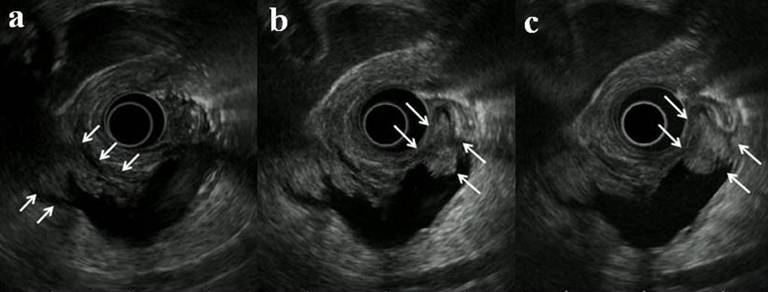

A 73-year-old woman was followed for mixed-type IPMN. The B-mode image showed mural nodules (maximum height: 6 mm) which were visualized in the MPD of the pancreatic head (Figure 1a). Both THE-P (Figure 1b) and THE-R (Figure 1c) modes revealed another nodule (height: 8 mm) which could not be readily detected by the B-mode, and more clearly visualized mural nodules in the MPD than the B-mode (Video1).

Figure 1a. A B-mode image clearly showed mural nodules (maximum height: 6 mm) in the MPD of the pancreatic head (arrows); Figure 1b. A THE-P mode image revealed another nodule (height: 8 mm) in the MPD near the papilla (arrows) and more clearly visualized mural nodules in the MPD; Figure 1c. A THE-R mode image revealed another nodule (arrows), similarly to the THE-P mode image. |